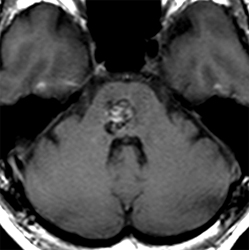

一名有高血壓史的62歲女性由于意識突然紊亂而被送往另一家醫(yī)院。CT掃描顯示存在原發(fā)腦橋出血。她接受了2周的保守治療。然而,她的癥狀沒有好轉,她被轉到德國INI醫(yī)院。入院時,她表現(xiàn)出意識障礙(GCS評分,13),左側偏癱(MMT評分,3),右側神經(jīng)III麻痹,左側面神經(jīng)(神經(jīng)VII)麻痹(HB級2)。發(fā)病后21天,她通過半枕外側入路進行手術?;颊叩囊庾R水平,運動功能,眼球運動和面神經(jīng)麻痹在術后早期開始好轉。術后MRI顯示完全切除腦橋血腫。她恢復后神志清,并且獨自步行出院。

腦海綿狀血管瘤案例

由于突然意識喪失和構音障礙,一名71歲男子被送往德國INI治療。入院時,他表現(xiàn)出意識障礙(GCS評分,13),右側偏癱(MMT評分,3),左側神經(jīng)III和神經(jīng)VI麻痹,左側VII麻痹(HB級2)。CT掃描顯示存在原發(fā)腦橋出血(下圖,左起二個)。在發(fā)病后6天,在家人提供書面知情同意書后,他通過跨半長位置的半長方位進行手術。血管通過菱形窩從面部三角區(qū)撤離.盡管他的眼球運動仍然受損,但他的意識水平,運動功能和面部麻痹在術后早期開始好轉。術后MRI顯示完全切除腦橋血腫。